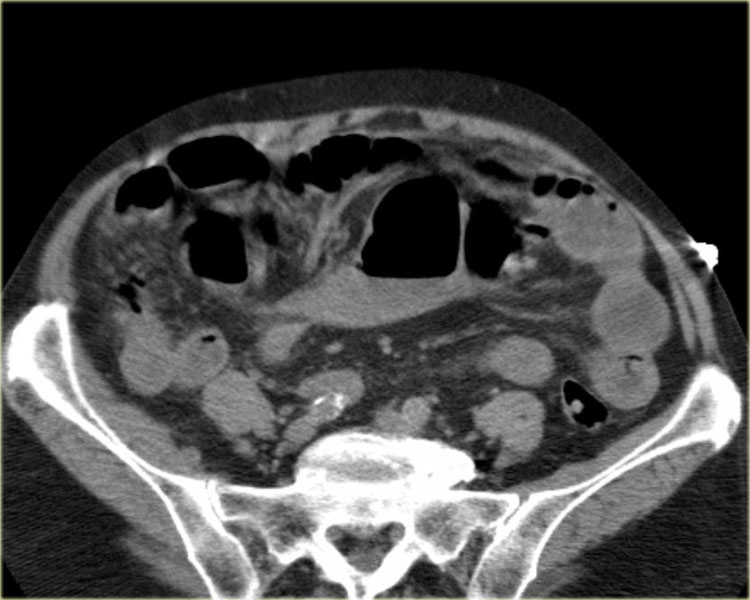

Tắc ruột dạng quai kín với các quai ruột giãn xếp theo hình nan hoa. Có dày thành ruột và phù nề mạc treo gợi ý thiếu máu cục bộ

Một hình ảnh quan trọng khác của tắc ruột dạng quai kín là các quai ruột non giãn xếp theo hình nan hoa với các mạch máu mạc treo hội tụ về một điểm trung tâm.

Hình ảnh này hầu như luôn do xoắn ruột non gây ra.

Các dấu hiệu thiếu máu cục bộ trong tắc ruột dạng quai kín tương tự như ở bệnh nhân thiếu máu mạc treo do các nguyên nhân khác:

- dày thành ruột

- phù nề mạc treo

- cổ trướng

- sự ngấm thuốc của thành ruột trong thiếu máu cục bộ có thể bình thường, tăng hoặc giảm.

Nếu quai kín dài hơn và định hướng vuông góc với mặt phẳng cắt, chúng ta sẽ thấy một cụm quai ruột như trong ca lâm sàng bên trái.

Đôi khi điều này khó nhận biết chỉ trên các lát cắt ngang và các tái tạo mặt phẳng coronal hoặc sagittal có thể hữu ích.

Trong ca này, cũng có phù nề mạc treo và cổ